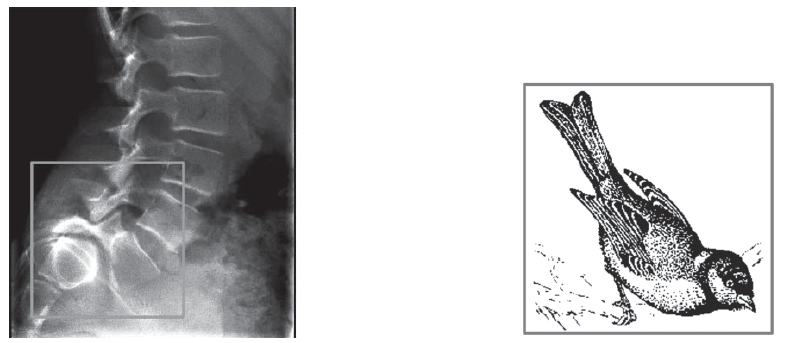

С легкой руки Г.И. Турнера в обиход ортопедов вошли симптом «горделивого лобка», «телескопического туловища». Вследствие изменения лордоза и смещения тела позвонка кпереди нередко на спондилограммах можно видеть запрокидывание остистых отростков трех нижних поясничных позвонков кверху – это рентгенологический симптом «воробьиных хвостов», который также был описан Г.И. Турнером.

Рис. 4. Рентгенологический симптом «воробьиных хвостов»